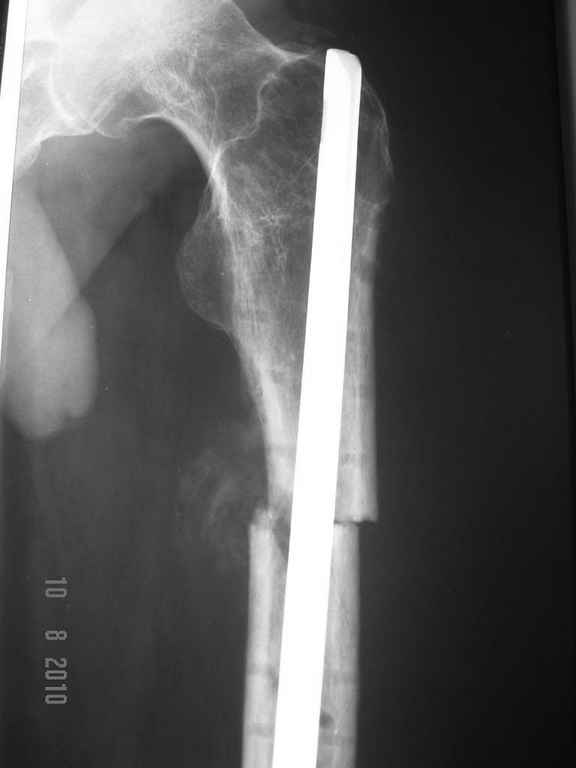

ДОбавил фото....

Условия больницы не блещут как собственно и финансовые возможности больного. Варианты типа БИОС, бусы с антибиотиками наверное так и останутся "вариантами". Пока интересует вопрос - остеомиелит? что делать?

Здесь, мне кажется, не только осложнение послеоперационной раны, а также имеется технические погрешности установки гвоздя. Трохантерная точка введения гвоздя является идеальной для антеградных гвоздей, но такие гвозди имеют изгиб в 4-5 градусов. Повело в варус за счет трансляции на диафизе, а также имеется подозрение на ротацию.

При желании, любой интрамедуллярный гвоздь с помощи пары шурупов в гвоздь или мимо гвоздя можно превратить в блокирующую конструкцию. Более стабильная конструкция дает лучше возможности ранней активности и нагрузки.

Поперечные переломы более стабильные в нагрузке, и учитывая, что с момента операции прошло не менее трех недель, сейчас можно разрешить полную нагрузку.